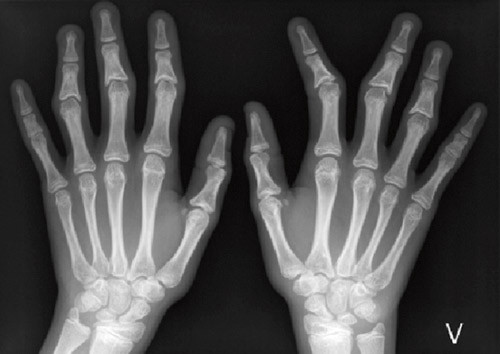

Grunnet mistanke om trikorhinofalangealt syndrom ble det tatt røntgenbilder av hendene, som viste korte falanger og kjegleformede epifyser. Røntgenundersøkelsene viste også forsinket skjelettmodning, svarende til 3,5 år. Pasientens høyde lå omtrent på 10-prosentilen, mens midtforeldrehøyden var i nærheten av 97,5-prosentilen. Kognitiv, sosial og øvrig utvikling var aldersadekvat.

En jente hadde fra 6 – 7-årsalderen fått langsomt økende skjevstillinger i flere fingerledd på begge hender. Senere ble det også påvist litt skjevt bitt. Røntgenundersøkelse før primærundersøkelsen viste kjegleformede epifyser i grunnfalangen på 1. finger bilateralt samt i midtfalangen på flere andre fingre.

Pasient 3 hadde tynt hår, kraftig nese med meget små nesevinger, antydning til retrognati, tynn overleppe, tynne øyebryn lateralt og deformerte fingre. Røntgen av hendene viste kjegleformede epifyser, spesielt proksimalt på midtfalangene. Hun hadde skjøre negler, liten plass til tennene, som var skjeve, men i normalt antall.

Pasient 4 hadde også tynt hår, et stort neseparti med meget små nesevinger og tynne øyebryn lateralt samt deformerte fingre (fig 2a), med kraftige ledd. Også her viste røntgen av hendene (fig 2b) kjegleformede epifyser. Hun hadde litt skjeve tenner i normalt antall samt skjøre negler.

Formaliserte diagnostiske kriterier for diagnosen trikorhinofalangealt syndrom er ikke blitt definert, men de nevnte ansiktstrekkene, forsinket vekst, korte og krokete fingre (fra 5 – 6-årsalderen), og forandringer i negler (6) er så karakteristiske at klinikere og genetikere som har erfaring med tilstanden, kan stille en sikker diagnose. Særegne kjegleformede epifyser ses hos så godt som alle med syndromet, og diagnosen er svært usannsynlig dersom man finner normale forhold ved røntgen av håndskjelett (2, 7).